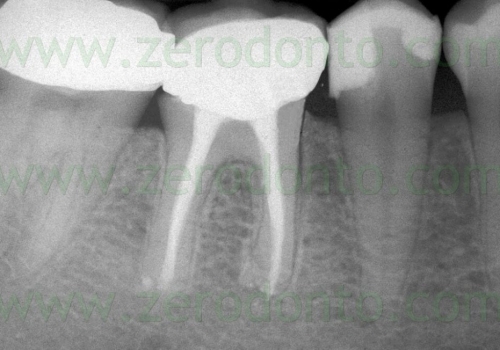

Bu zaman bəzi hallarda kanal müalicəsinin yenidən icrası (endodontik reviziya) mümkün olsa da, bir çox hallarda bu və ya digər səbəbdən həyata keçirilməsi mümkün olmur. Bu zaman əsas tətbiq edilən müalicə metodu dişi çəkməmək şərti ilə, iltihab ocağının uzaqlaşdırılmasını təmin edən – diş kökünün rezeksiyası metodudur. Bu əməliyyat vasitəsilə iltihab ocağı diş kökü ilə birlikdə kənarlaşdırılır və kök kanalları xüsusi metodla yenidən işlənir və doldurulur. Əməliyyat əsasən yerli ağrısızlaşdırma altında, xüsusi böyüdücü vasitənin tətbiqi ilə həyata keçirilir.

Uğurla tətbiq edildiyi halda uzun illər ərzində uğur vəd edən bir müalicə metodudur. Bu əməliyyat ağıl dişləri və bəzi hallarda 7-ci dişlər (ikinci böyük azı dişləri) istisna olmaqla digər bütün dişlərdə uğurla həyata keçirilə bilir. Müalicə metodunun uzunmüddətli uğurlu olmasında əməliyyatönü müayinənin ciddi şəkildə aparılması və dişlərin doğru seleksiyası xüsusi əhəmiyyət kəsb edir.